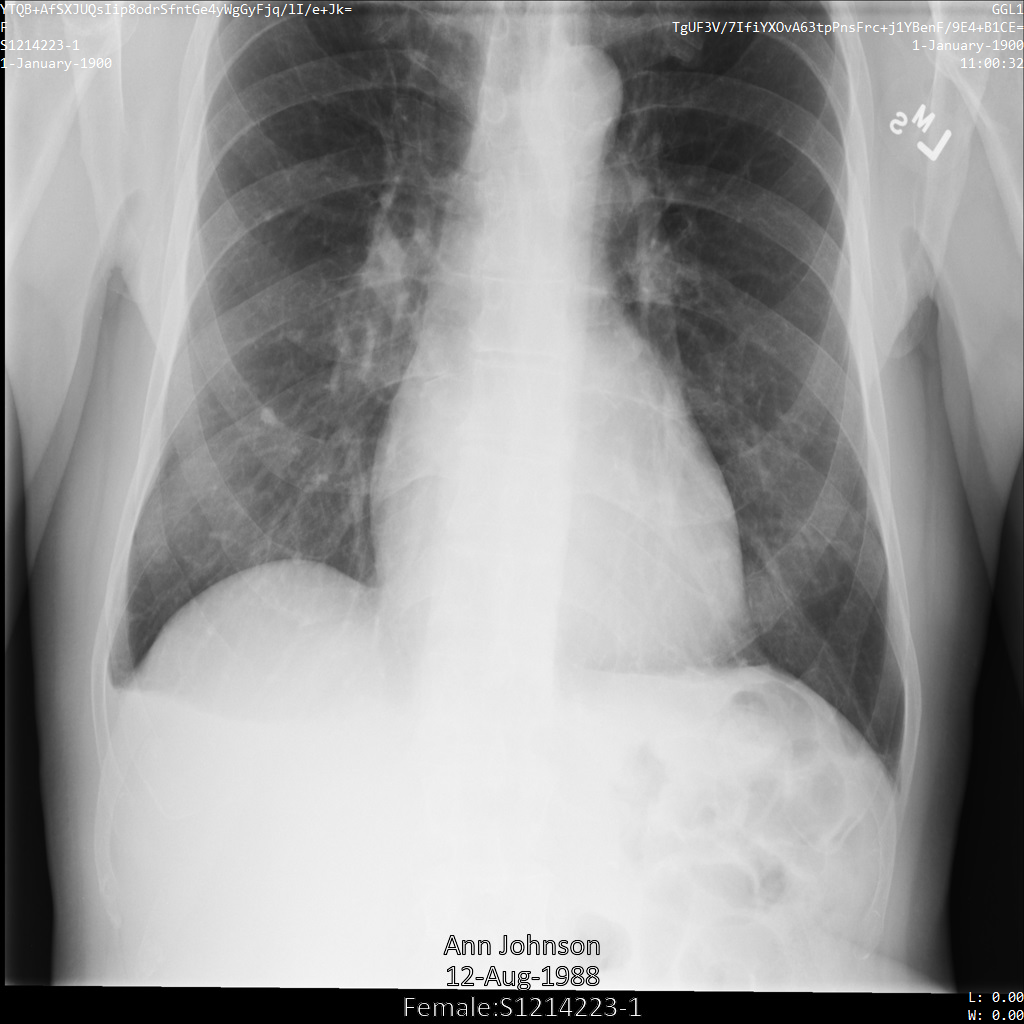

将图片提交到 Cloud Healthcare API 后,图片显示如下。虽然图片顶部角落显示的元数据已被遮盖,但图片底部的烧屏受保护健康信息 (PHI) 仍然保留。如需一并移除烧屏文字,请参阅遮盖图片中的烧屏文字

dicom_keeplist